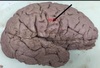

1. Identify the highlighted (red) area. 2. What structure is the black arrow pointing to? 3. What structure is the blue arrow pointing to? 4. What structure is the green arrow pointing to?

1. Occipitotemporal Sulcus 2. Parahippocampal Gyrus/ uncus 3. Medial Occipitotemporal gyrus 4. Lateral Occipitotemporal gyrus